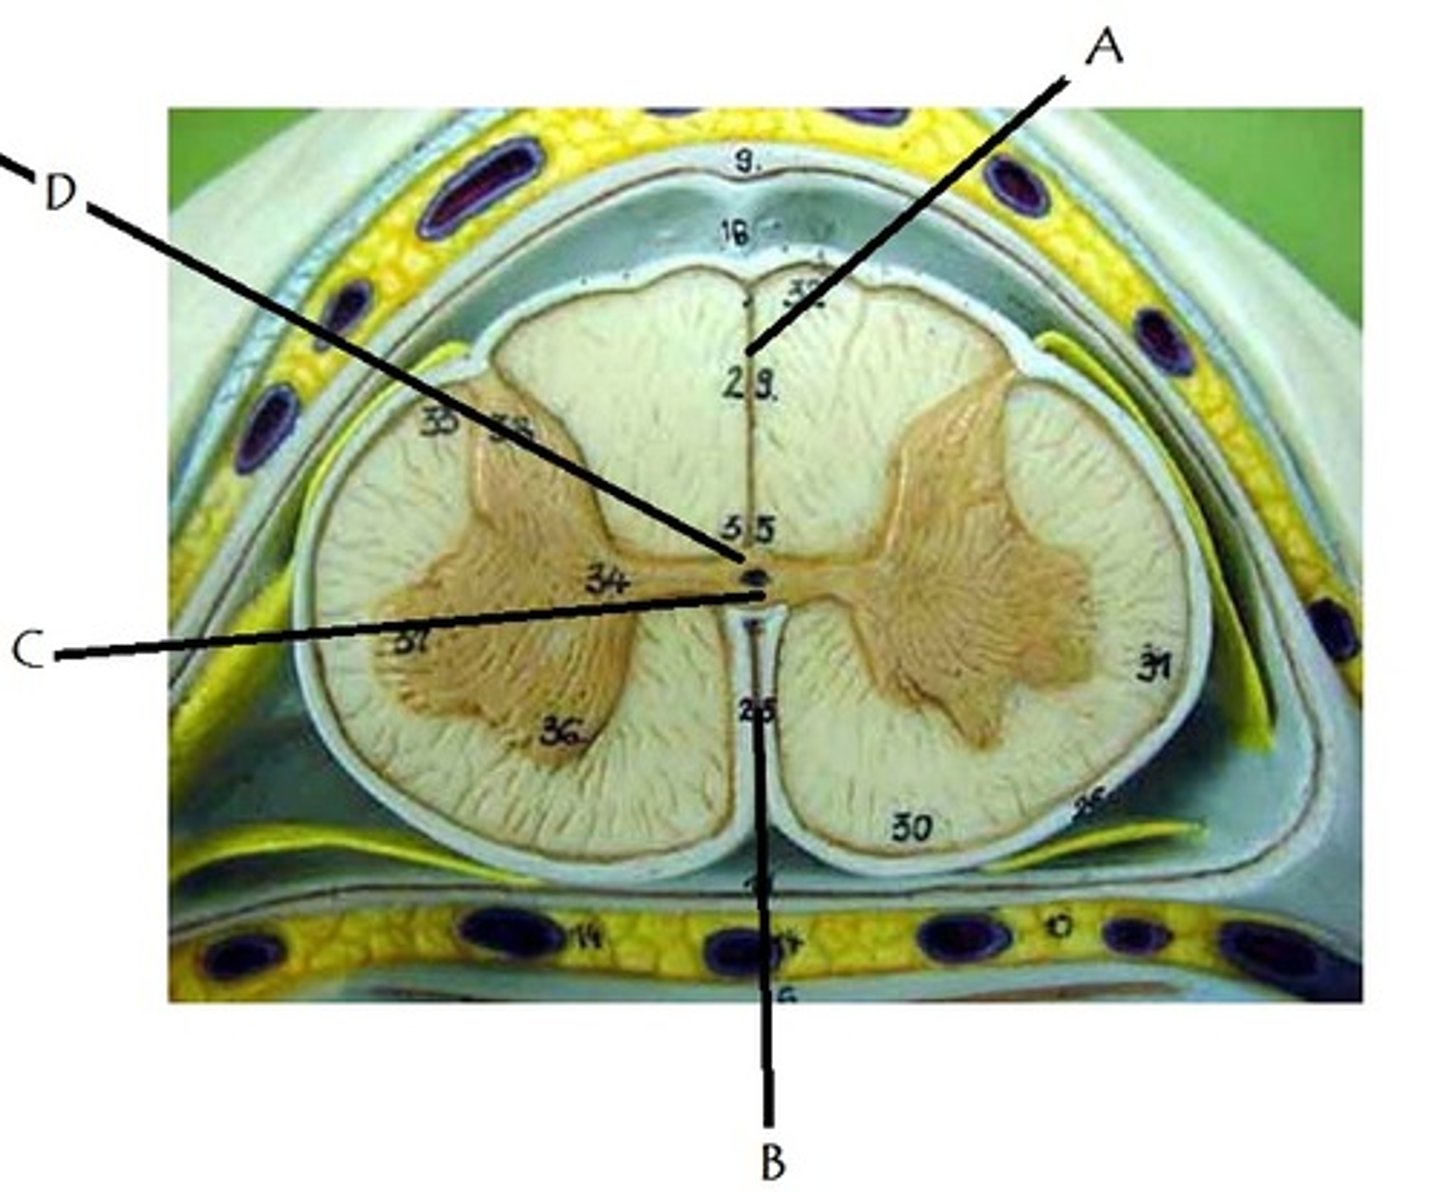

Identify A

lateral white column

Identify B

anterior white column

Identify C

anterior median fissure

A

Which lettered area does not contain CSF?

ventral root

dorsal root ganglion

dorsal root